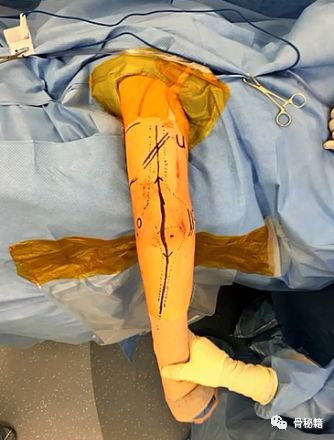

术野显露,术前划线,需要画出中轴线,桡骨头,尺神经,桡神经,骨折断端

国外有那种无菌的止血带,可以术中应用,国内好像没有,一般不用